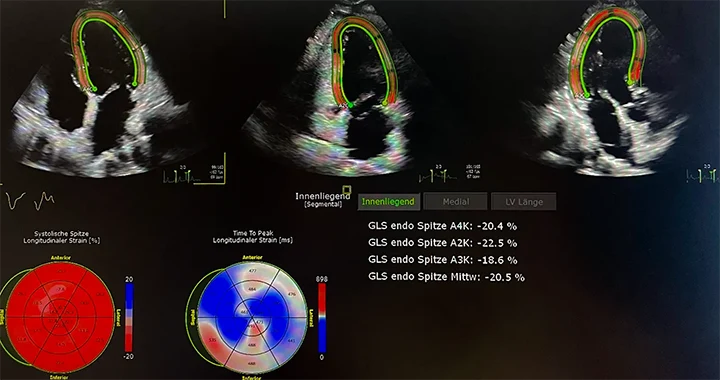

Strain-Analyse (Deformationsanalyse)

Die Strain-Analyse misst die Dehnbarkeit des Herzmuskels – also, wie gut sich das Herz bei jedem Schlag zusammenzieht. Mit modernster Speckle-Tracking-Technologie analysieren wir feinste Bewegungsmuster des Herzmuskels in Echtzeit. So können wir bereits frühzeitig Funktionsstörungen erkennen, bevor sie in anderen Messwerten sichtbar werden.

Typische Einsatzgebiete sind:

- Verlaufskontrollen bei Chemotherapie (kardioonkologische Überwachung)

- Früherkennung bei Amyloidose, Bluthochdruck oder Diabetes

- Beurteilung der Funktion von linker Herzkammer (GLS), linkem Vorhof (LA-Strain) und rechtem Ventrikel (RV-Strain)